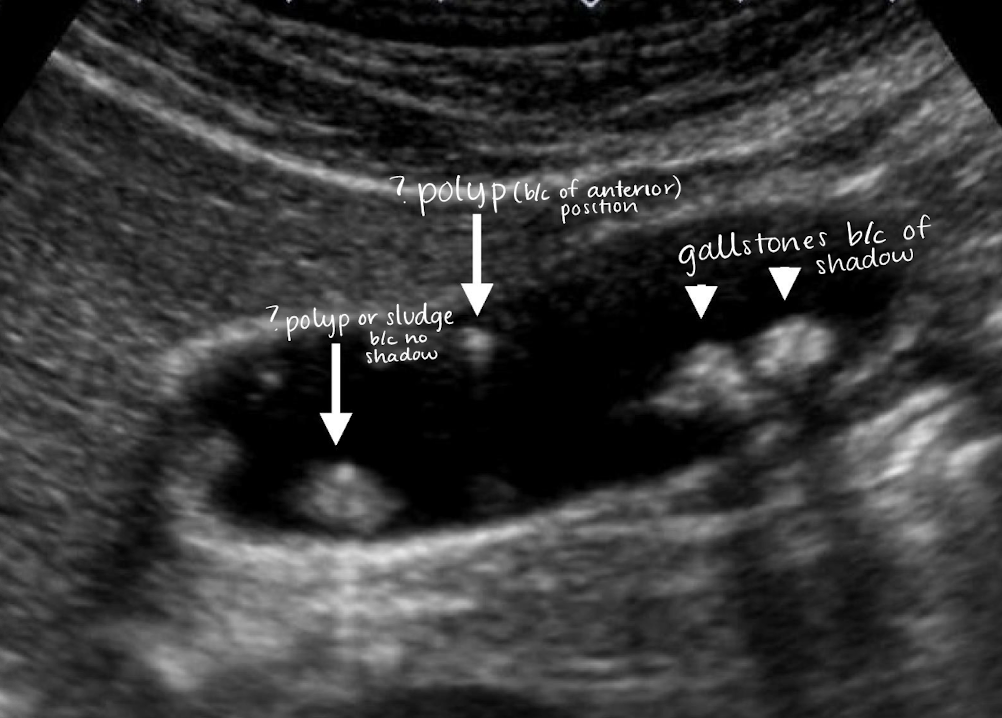

SONO: cholelithiasis

twinkle artifact

posterior shadow (due to refraction, impedance, intensity of the sound beam, and stone(s) size)

WES (wall echo shadow)

indicative of a stone-filled GB (GB is a packed)

3 arched-shaped line

shadow posterior to 3rd line

??

cholelithiasis

calcified stones with posterior shadowing

polyp

small, well-defined soft tissue projection adhering to GB wall

SONO:

non-shadowing

non-mobile